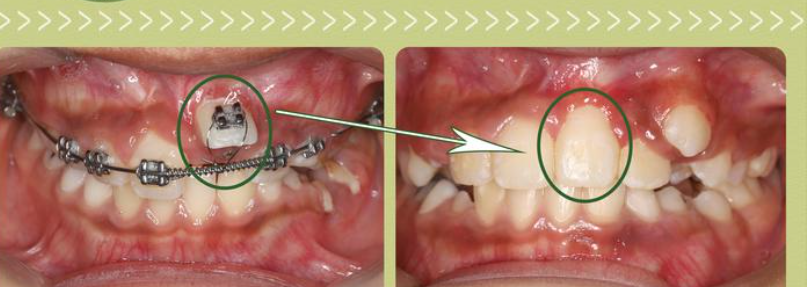

上下牙咬合错位不仅对口腔健康产生影响,还会影响面部外貌和自信心。不对称的面部轮廓、突出的下颌、露出的牙龈等问题,会让人感到尴尬和不自在。牙齿矫正对于改善面部外貌和塑造自信心至关重要。